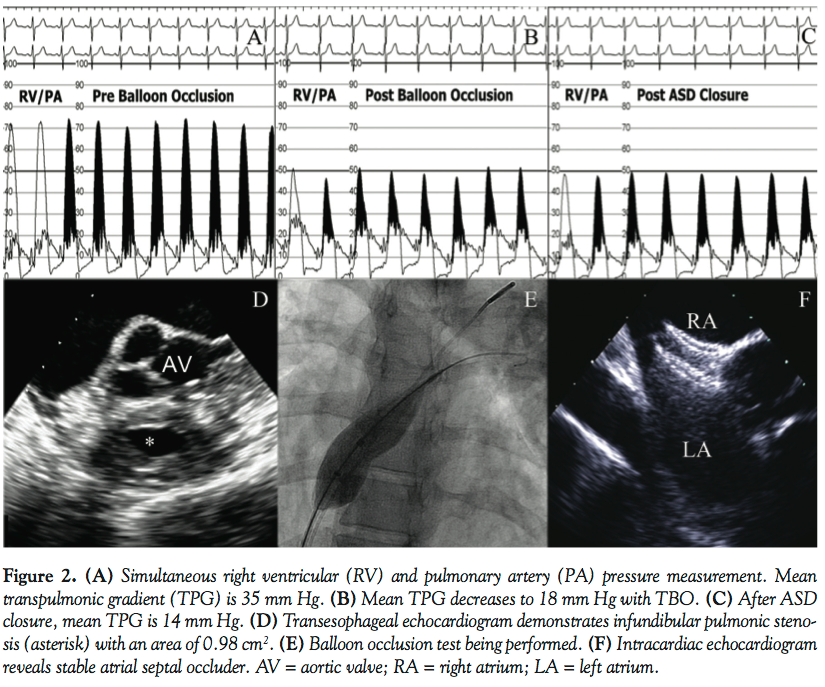

A 74-year-old woman with progressive dyspnea on exertion was diagnosed with a 16 mm secundum ASD and diastolic dysfunction as evidenced by elevated left ventricular filling pressures (Figure 1). Cardiac catheterization revealed Qp:Qs of 2.5:1. TBO demonstrated a rapid increase in mean pulmonary capillary wedge pressure (PCWP) to 30 mm Hg (19 mm Hg at baseline). A self-fabricated 18 mm Amplatzer cribriform atrial septal occluder (St Jude Medical) was then deployed to prevent acute volume overload of the left ventricle. Upon device closure, mean PCWP was 20 mm Hg.